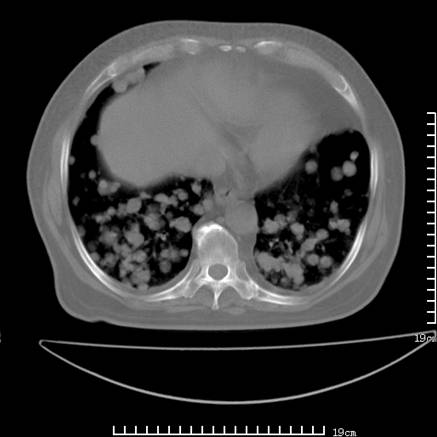

张男,75岁,干咳半年余,小便不利二年,b超检查前列腺增大,未见明显肿块;前列腺癌血生化检查多项指标明显增高。

双肺内多发转移瘤,纵膈淋巴结转移。来源前列腺?建议盆腔mri进一步检查。

双肺转移满了。

两肺广泛转移瘤。